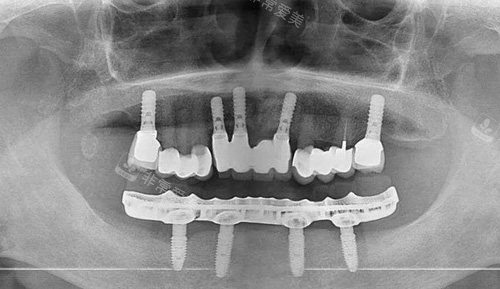

全口种植牙解析图

全口种植ct图片